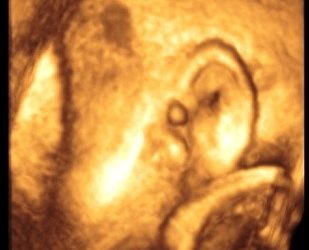

Primigravida di 28 anni, a 12 settimane + 3 giorni, giunta alla nostra osservazione per sottoporsi a screening delle aneuploidie...

Presentiamo il primo caso elaborato dai colleghi in formazione della Clinica Ostetrica Ginecologica di Ancona diretta dal Prof. A. Ciavattini:...

Caso clinico Primi gravida di 31 anni esegue screening del primo trimestre che la mette a rischio per patologie cromosomiche....